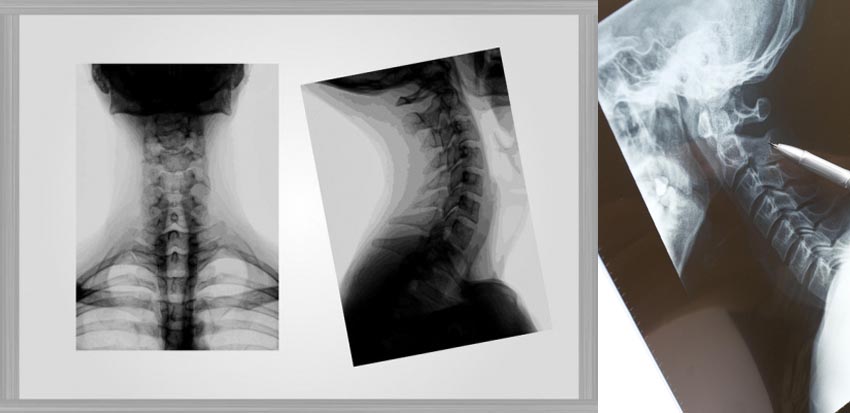

Cervical Spine Surgery

There are seven bones in your cervical spine and these are referred to as the vertebrae. At one end it is fixed to your skull and at the other, it is joined to the thoracic spine, just behind your chest.

Your cervical spine plays a number of vital roles:

• It protects your spinal cord, which runs inside it

• The two vertebrae at the top allow your head to move sideways

• The rest of the vertebrae make it possible to tilt your head and neck

• Your vertebrae feel the impact of movement, so there is a disc between every set of two vertebrae that acts as a shock absorber to help protect them.

Cervical spine surgery is generally performed to treat neck pain, numbness, tingling, and weakness resulting from cervical degenerative disc diseases or a symptomatic cervical herniated disc. The approach for surgery varies a lot depending upon the root cause of the problem and patient’s medical history.

Although there are some medications available to help with pain caused by cervical cervical spine issues, if pain and disability are severe and unresponsive to nonsurgical treatments, spine surgery may be a reasonable option.